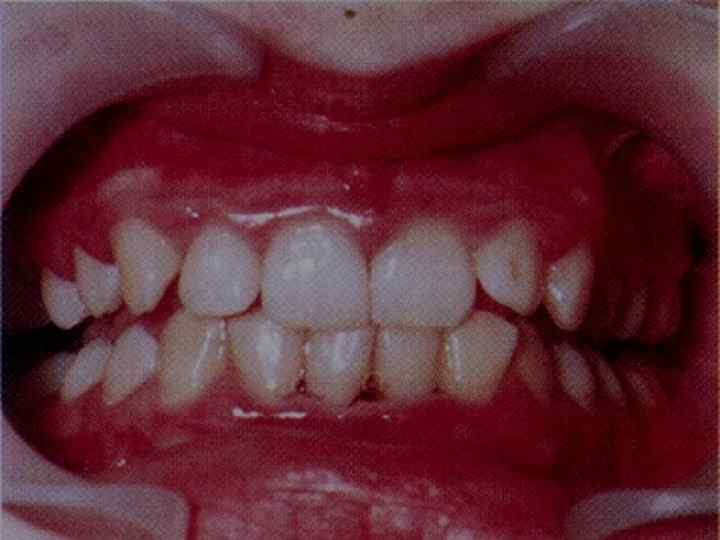

Клиникалық белгілері • Жылдам дамитын пародонт қабынуының атипиялығы пародонт тіндерінің бұзылысқа ұшырауы жастық шақта басталады: 17– 20 жастан, дәстүрлі емге берілмейді және нәтижесі нашар. .

• ЖДПҚ клиникалық белгілері : • Пародонт тіндеріндегі деструктивті өзгерістер балалық шақтан кейінгі немесе ерте жастық шақта басталады. • Пародонттағы қабыну үрдісінің төмендігіне қарамастан, сүйек тінінің жайылған деструкциясының болуы • Басқа науқастармен салыстырғандағы бірдей тіс қақтарында, пародонттың ауыр бұзылыстары • Емнің нәтижесіздігі немесе нәтиженің қысқа мерзімділігі.